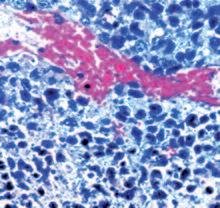

Questo vale anche per le cellule leucemiche. Una caratteristica di questa forma di tumore del sangue è l’eccesso di produzione di globuli bianchi, i pazienti affetti da leucemia muoiono principalmente, perché queste cellule bloccano la circolazione del sangue. In molti casi i leucemici muoiono per il cedimento di vari organi, in particolare ‘gli organi filtro’: il fegato e la milza. Milioni di globuli bianchi invadono questi organi attraverso il flusso sanguigno. Queste cellule cancerose producono immense quantità di enzimi che digeriscono il collagene, digerendo letteralmente questi organi dall'interno.

La foto nella pagina a fianco mostra una sezione trasversale al microscopio del fegato di un paziente con ‘leucemia linfatica’. Ciascuno dei piccoli puntini viola nella foto è un globulo bianco (in questo caso linfocita) che ha invaso il tessuto del fegato (aree rosa).

Considerando l’enorme quantità di questi puntini viola e il numero di enzimi che assimilano il collagene che ciascuno produce, è facile prevedere l’ingente distruzione del tessuto connettivo e il danno apportato all’organo da questo tipo di cancro.

La leucemia è un buon esempio di come la comprensione dei meccanismi delle cellule tumorali, la produzione di enzimi che digeriscono il collagene da parte dei globuli bianchi, per poter studiare terapie efficaci.

Immagine al microscopio della leucemia linfatica

Globuli bianchi affetti di cancro (linfociti) invadono il fegato L’enorme quantità di collagenasi prodotte da queste cellule distruggono l’organo e causano insufficienza epatica.